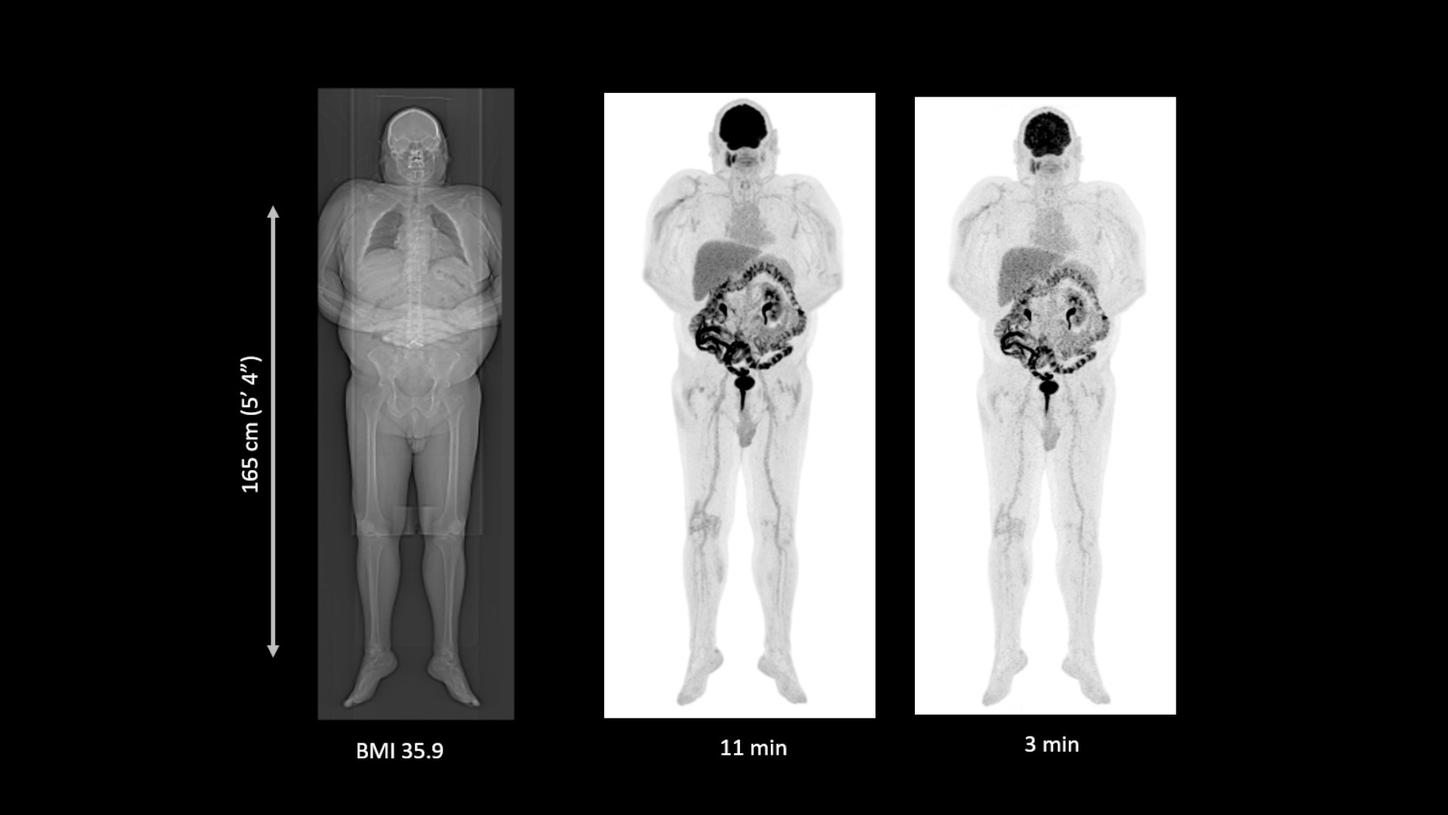

Greater scale with ease

Increase sensitivity and extend coverage up to 48-cm aFOV.